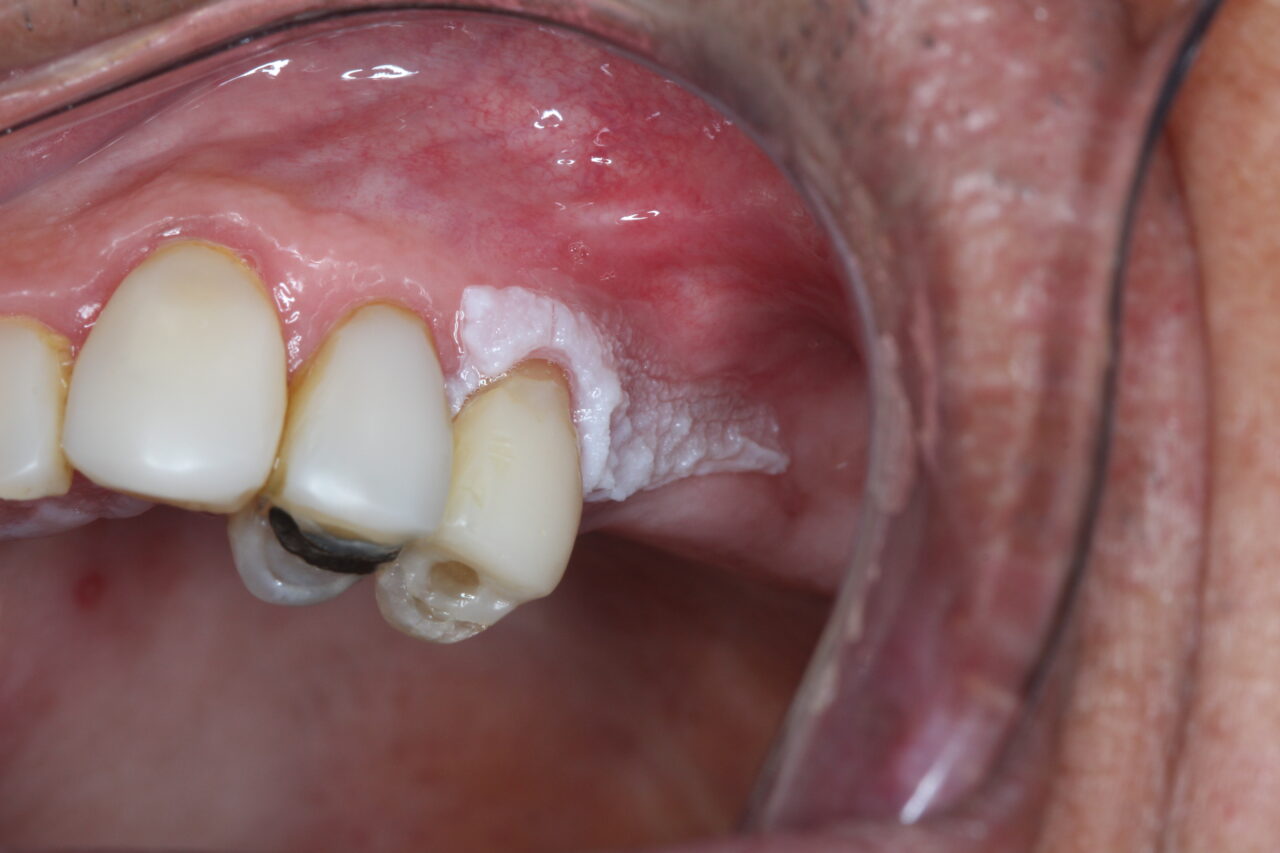

trauma crônico na boca

Uma mancha branca persistente na boca pode ter várias causas. Quando ela não sai ao raspar e não pode ser diagnosticada clinicamente como outra lesão comum, pode ser chamada de leucoplasia. Esse é um termo clínico usado após excluir outras doenças. Nem toda leucoplasia é grave, mas toda mancha branca persistente deve ser avaliada por […]